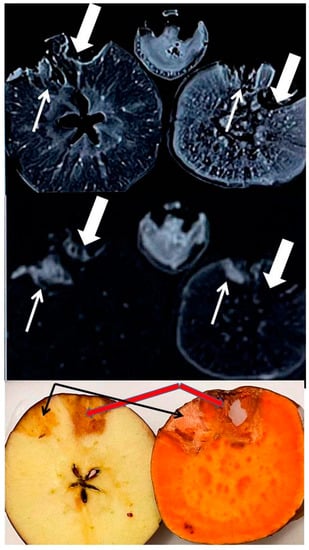

1.1. Radiological Contrast Agents and Transmetallation: An Environmental Issue

1.2. X-ray Absorption by Endogenous and Exogenous Minerals in Carbohydrate-Rich Fruit Matrix

1.3. Positive and Negative Signal Enhancement in Proton MRI by Endogenous and Exogenous Minerals

3.3. X-ray Imaging

3.4. MR Imaging